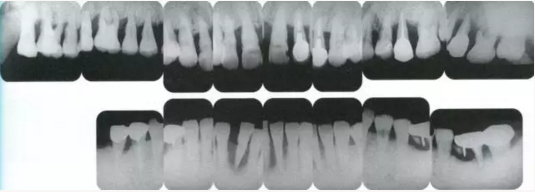

X光片。牙槽骨明顯缺失。

同時期的X光片。

佩戴最終修復(fù)體時的X光片。骨邊緣水平平坦,探診值維持在1~2mm。